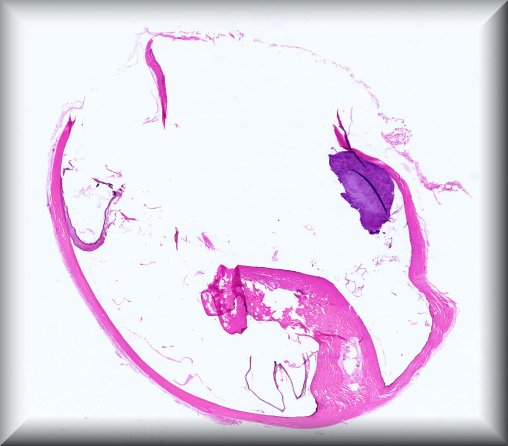

Martina Herwig-Carl (Bonn): 57 year old woman with a blind painful eye and history of intrvitreal bevacizumab injections, tumour biopsy and brachytherapy for uveeal melanoma followed by several proceedures for high intraocular pressure resulting finally in enucleation. |